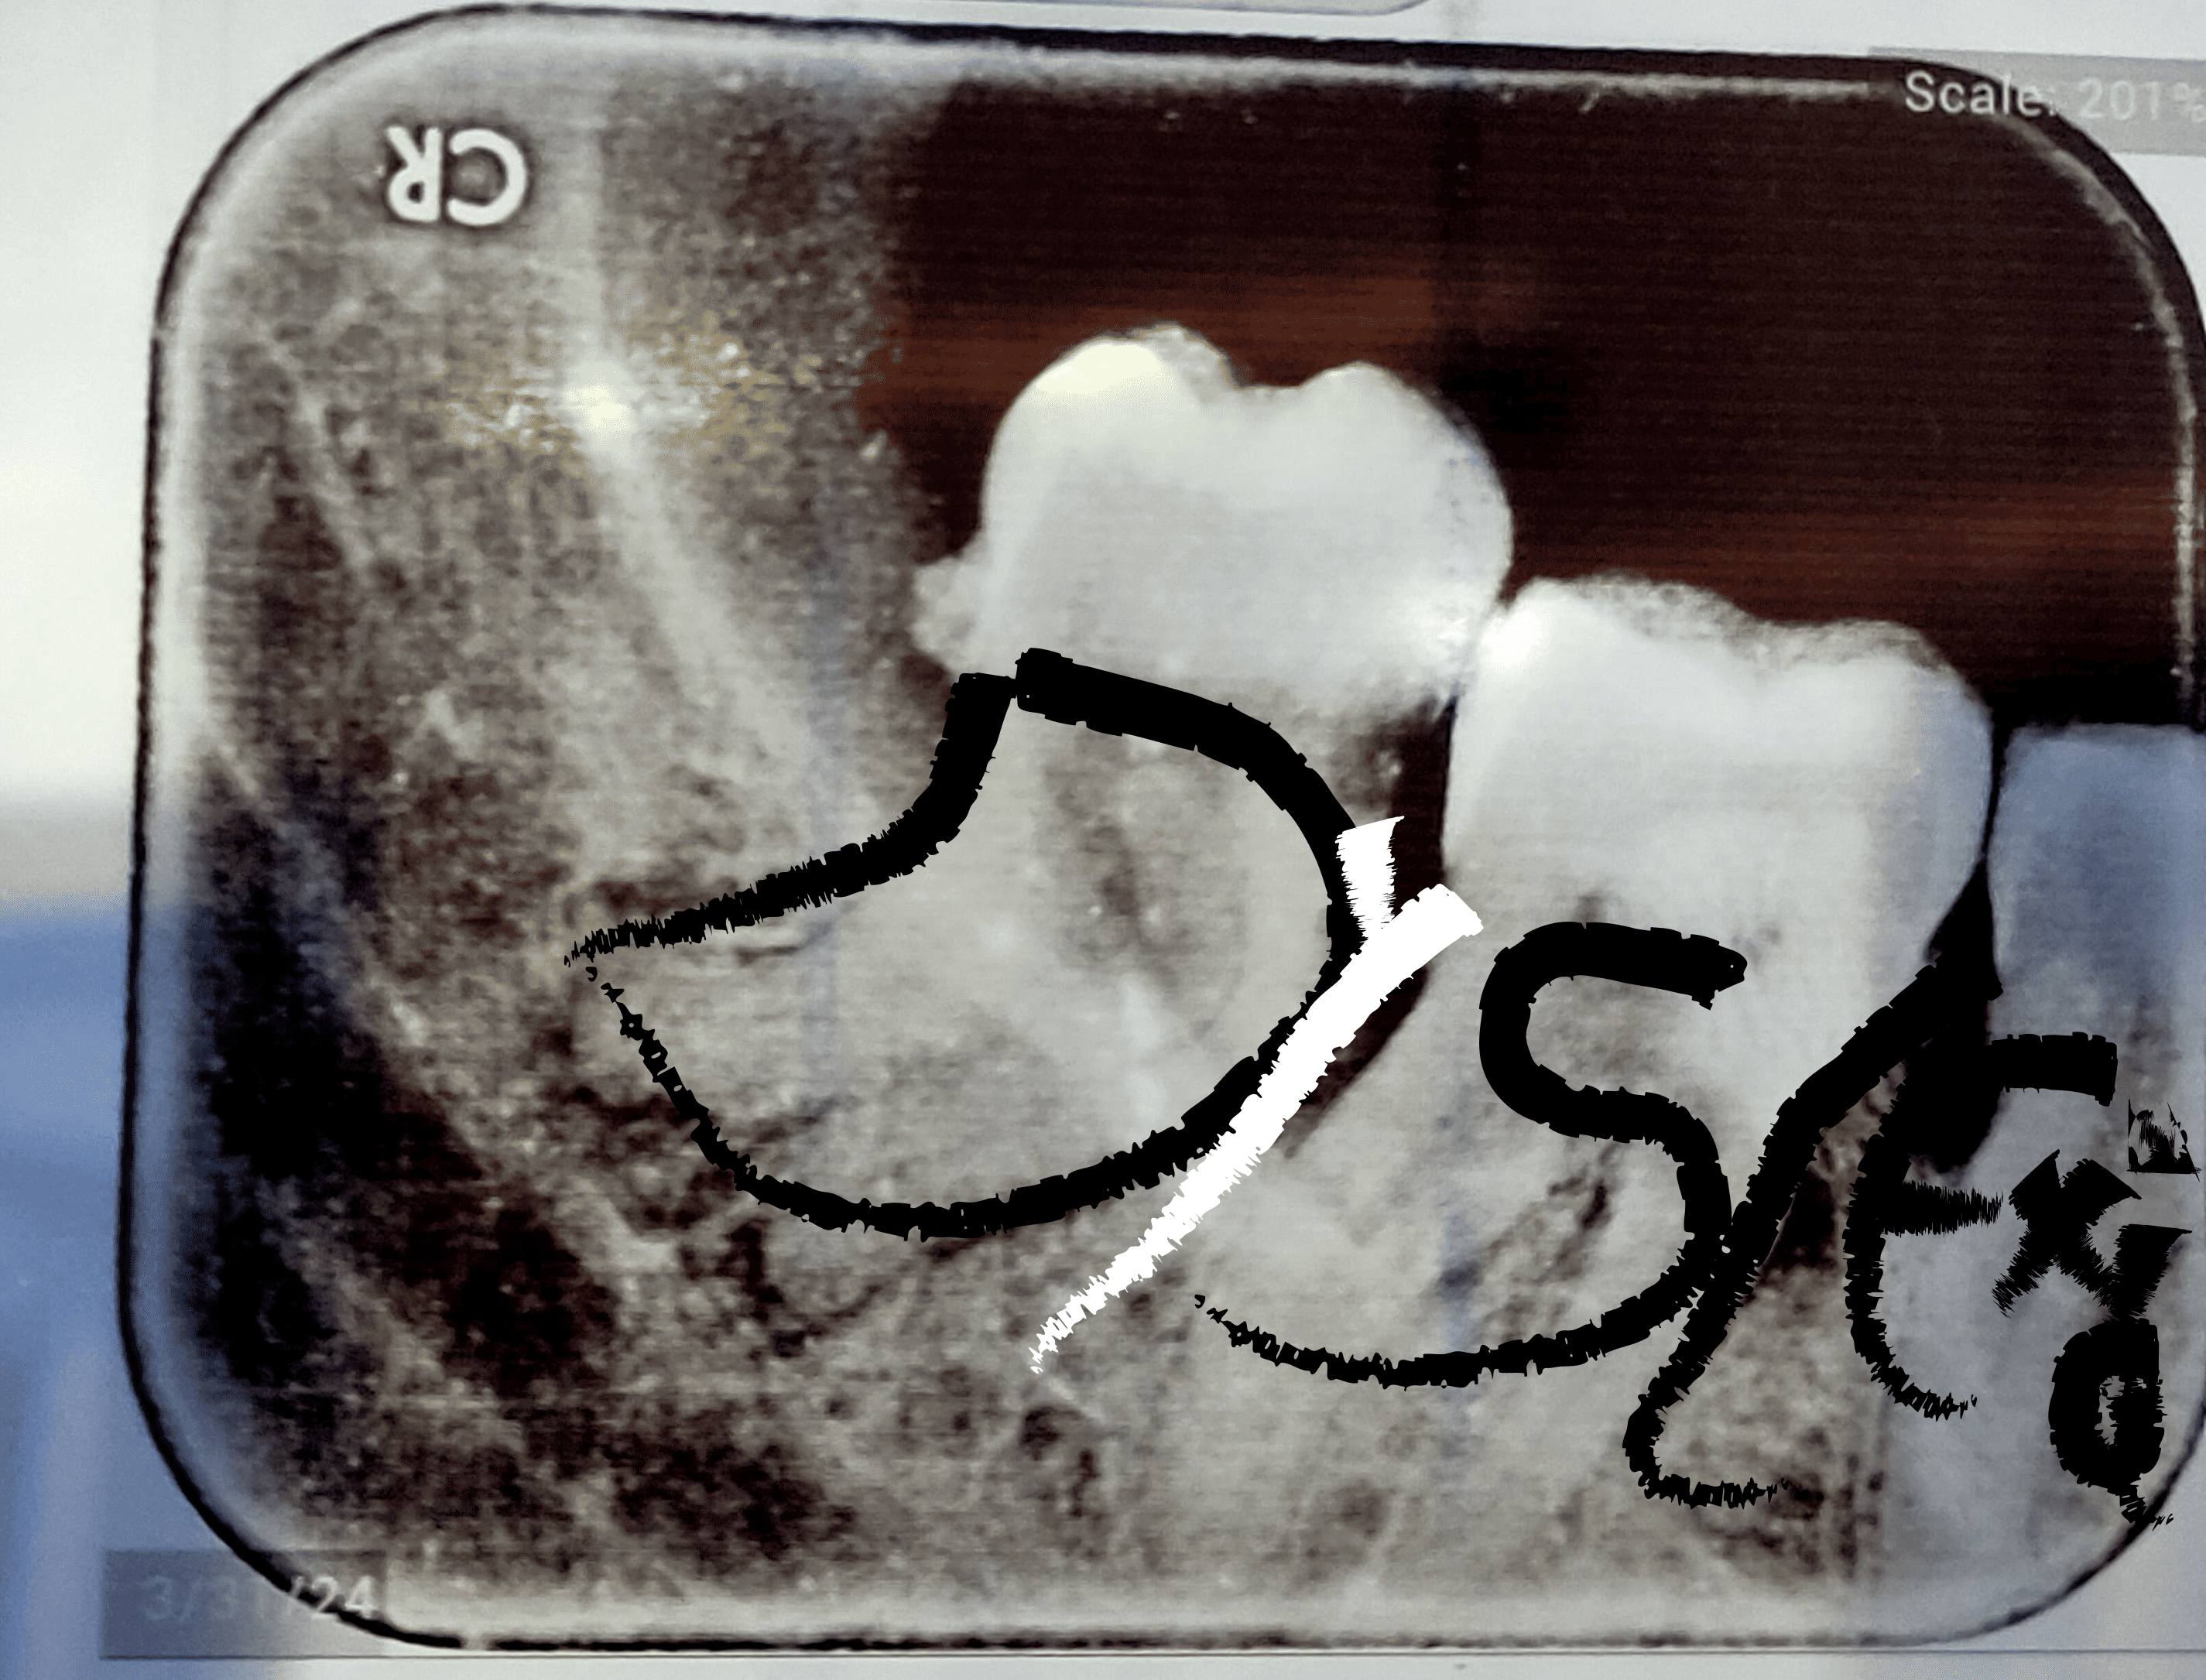

In the land of enamel and x-rays, I learned the art of dentistry—but my textbooks fought me.

Words like "periodontitis" wiggled like loose teeth. "Why does everyone else read this so easily?"